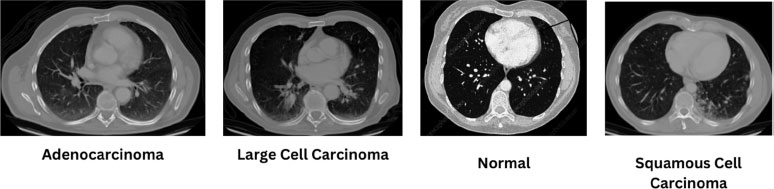

The dataset required for the prediction of the nature of lung cancer using the CT-Scan image is provided by Mohamed Hany, Chest CT-Scan images Dataset, Version 1 Retrieved August 2023 from https://www.kaggle.com/ datasets/mohamedhanyyy/chest-ctscan-images?datasetId= 839140. This dataset is used to train a customized “VGG16 Convolutional Neural Network” model to predict the three types of cancer found in the lungs, namely: “Adenocarcinoma”, “Large Cell Carcinoma”, “Squamous Cell Carcinoma” or the Normal Lung image. The categories of images contained in this dataset are listedin Table 2. An example of a CT-Scan image from each type of Lung Cancer is illustrated in Fig. (2). The software required is Python for Data Manipulation and Coding, TensorFlow for the implementation of Deep Learning and training the Convolutional Neural Network, and Jupyter Notebook for the integrative Python document.

The “VGG16” approach to predicting the type of Lung Cancer using “Convolutional Neural Networks” yields an accuracy of 92.53%. In the test data, the model delivered an accuracy of 90.79%. The different types of cancer are classified using the shape of the tumour in the CT scan automatically by the model (features for the classification). Table 3 demonstratesthe classification report for the Lung cancer type classification on the test set.